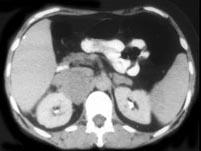

问题 男,65岁,腋下触及肿大包块,全身浅表淋巴结肿大,请结合所提供图像,选择最佳答案 ( )

选项 A、双侧肾上腺转移瘤 B、肾上腺癌 C、双侧肾上腺增生 D、双侧肾上腺淋巴瘤 E、双侧肾上腺腺瘤

答案 D